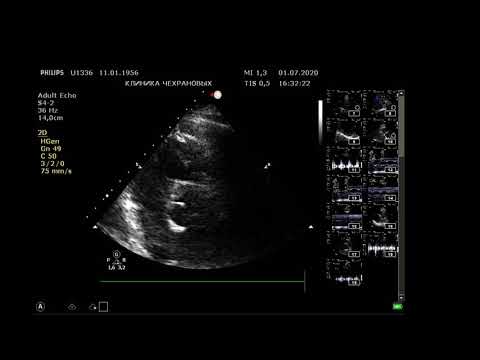

Эхокардиография. Разбор случая с АОРТАЛЬНЫМ СТЕНОЗОМ, низкой ФВ, ФП, ДИЛАТАЦИЕЙ всех полостей.

В данном видео разберем случай с аортальным стенозом с низкой фракцией выброса. Рассмотрим как узнать степень стеноза при низкой фракции выброса. Полный протокол эхокардиографии. Покажу как делать измерения, и как наприсать ОПИСАНИЕ и ЗАКЛЮЧЕНИЕ. Доступные онлайн уроки можно посмотреть и приобрести по ссылке: